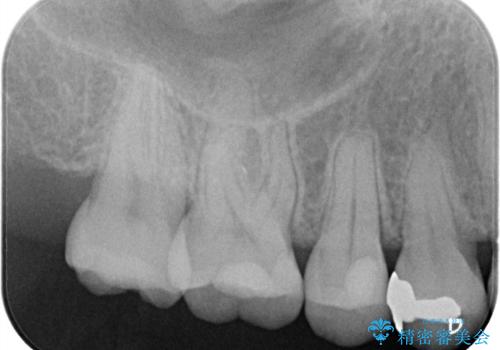

【セラミックインレー】むし歯の治療

- 定期検診にてむし歯を認めたため、セラミックインレーにて修復を行いました。

e-max プレスインレーにて修復治療を行っているため適合性及び審美性の高い治療を行うことができます